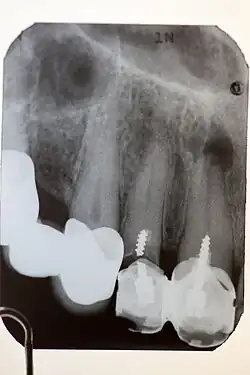

Stiftaufbau

Stiftaufbau an Zahn 11 und 12, der nicht dem heutigen Standard entspricht: zu kurz, geschraubt, gebrochen an Zahn 12, ohne Wurzelfüllung, Wurzelgranulom an Zahn 11